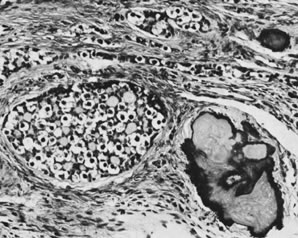

On microscopic examination, the granulosa cell tumor can be divided into two major subtypes, adult form and juvenile form, which differ strikingly in their patterns and cytologic features. The adult granulosa cell tumor is occasionally composed almost entirely of granulosa cells, with few or no accompanying thecal or fibroblastic elements, but more often the latter are present in some amount and may be substantial. The granulosa cell component of the tumor has a variety of patterns. The well-differentiated form most commonly has a microfollicular (Fig. 2), trabecular (Fig. 3), or insular pattern, or a combination of the three. Rarely, the pattern is macrofollicular, with the tumor composed of large follicles resembling normally developing follicles. Less well-differentiated tumors typically have a diffuse or sarcomatoid pattern, characterized by a sea of cells with little or no intervening stroma (Fig. 4); this type of tumor is particularly apt to rupture. Sometimes a watered-silk or zigzag (gyriform) pattern is seen. The stromal element of the tumor may consist of fibroblasts that have laid down considerable collagen, as well as cells that resemble theca externa, theca interna, or theca lutein cells.

Fig. 2. Granulosa cell tumor, microfollicular pattern with Call-Exner bodies (magnification, ×290).(Scully RE, Morris JM: Functioning ovarian tumors. In Meigs JV, Sturgis SH [eds]: Progress in Gynecology, Vol 3. New York, Grune & Siralton, 1957, by permission.)

Fig. 3. Granulosa cell tumor, trabecular pattern (magnification, ×200).(Serov SF, Scully RE, Sobin LH: Histological Typing of Ovarian Tumours. Geneva, World Health Organization, 1973.)

Fig. 4. Granulosa cell tumor, diffuse pattern (magnification, ×200).(Scully RE: Ovarian tumors with estrogenic manifestations. Contemp Ob Gyn 10:83, 1977.)